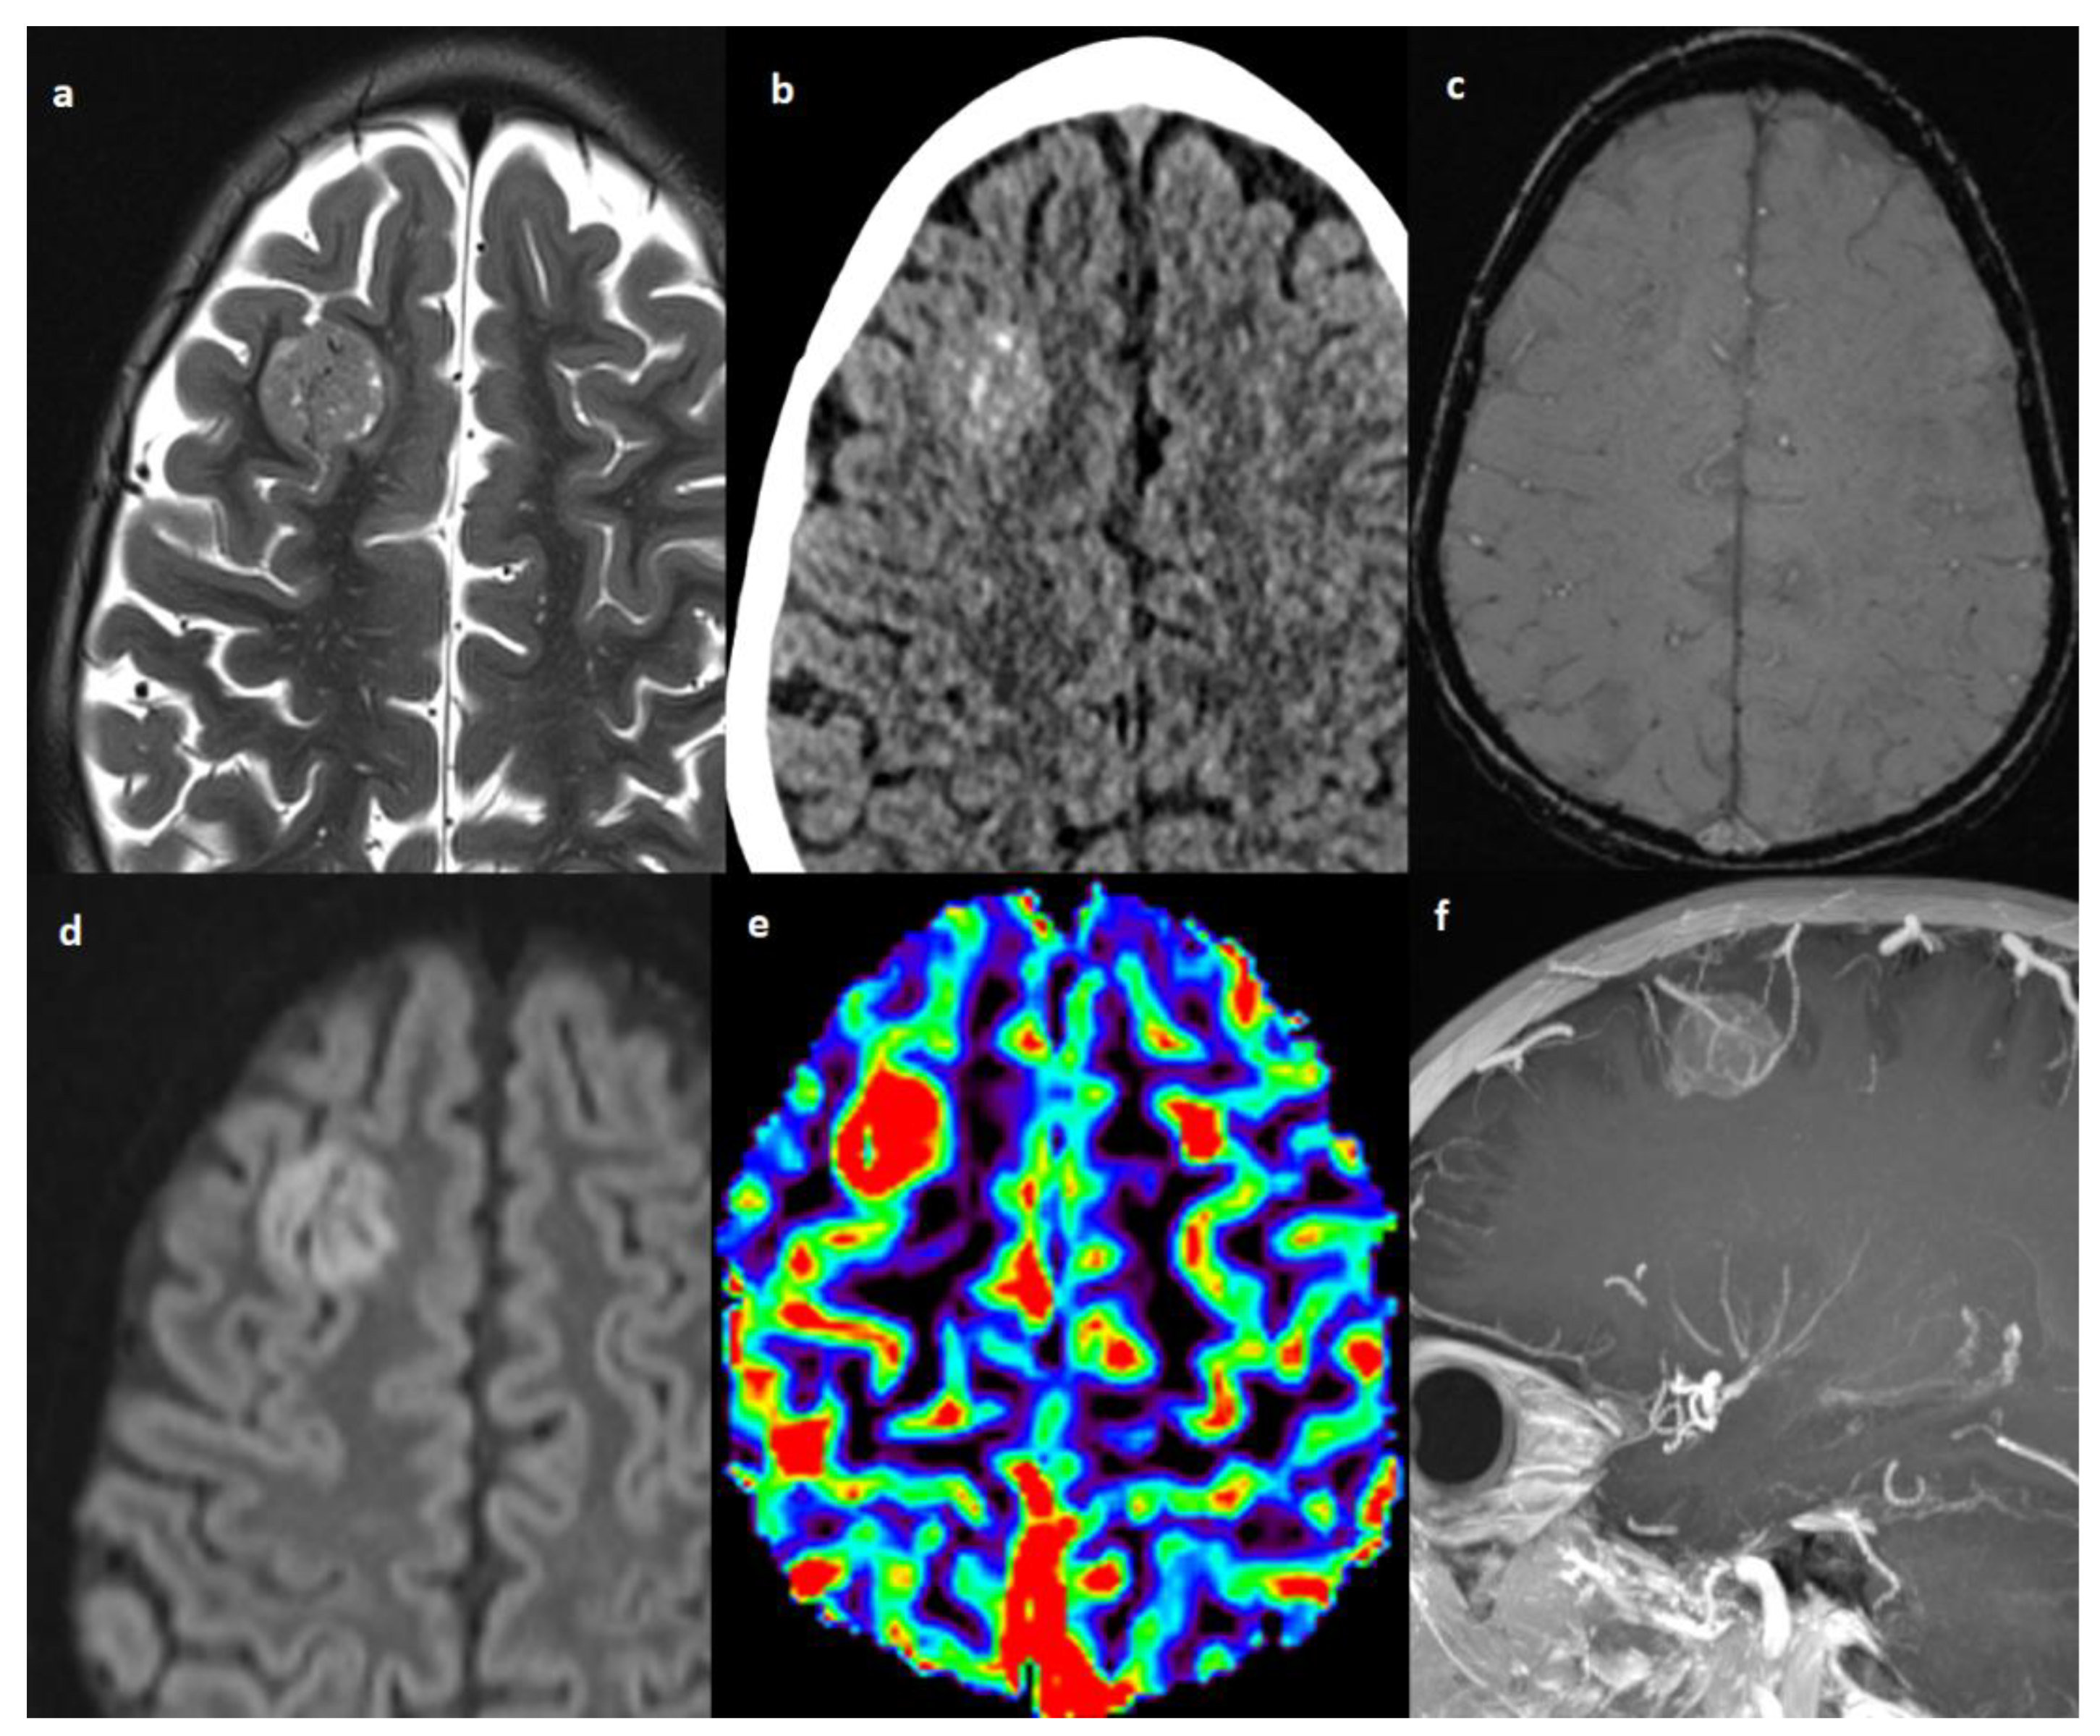

| 6 | brain parenchyma | right frontal lobe | 1 | 20 × 20 × 19 | CT MRI | yes | High | no | yes | no | restricted | increased | positive |